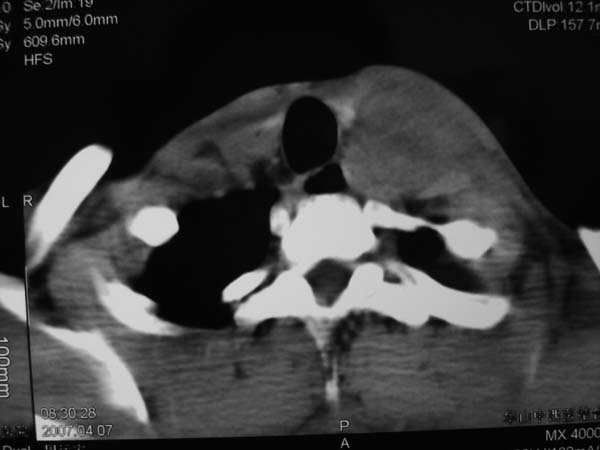

患者男性,37岁,农民,自觉左颈部肿大三天,无其它不适。

左侧颈部软组织密度肿块,界限清楚,形态不规则,占位效应明显。考虑:1 淋巴瘤。2 神经源性肿瘤不除外。

左颈部占位,病灶沿间隙分布,密度混浊,结合病史肿大三天,考虑1,炎症病变,建议增强。2,颈部血管性病变。

病灶边界较清,密度不均,其内可见坏死灶,左侧甲状腺受压,考虑神经源性肿瘤可能性大,建议穿刺活检。

病程短,症状轻,颈内动静脉显示不清,考虑血管病变。建议增强扫描。贸然穿刺可能会引起出血。

病灶边界较清,密度不均,其内可见坏死灶,左侧甲状腺受压,考虑神经源性肿瘤可能性大。